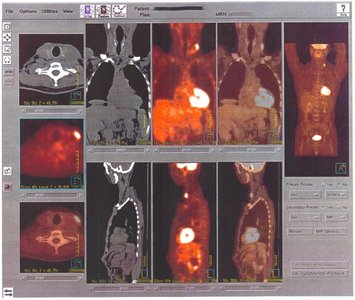

Radioisotopes are used in diagnostic procedures, such as PET scans, to track metabolic activity.